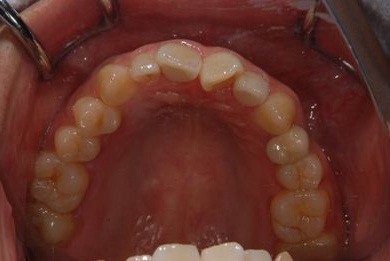

インプラントの症例写真 IMPLANT

インプラント治療+セラミック治療

| 治療内容 | インプラント1本、メタルボンドセラミッククラウン1本、オールセラミッククラウン2本(オールセラミック用土台2本) | ||||||||||||||||||||||||||||||||